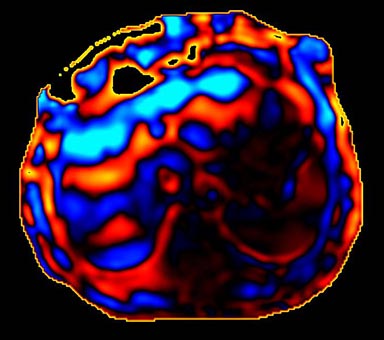

Figure 9. Color wave image: 4 phases